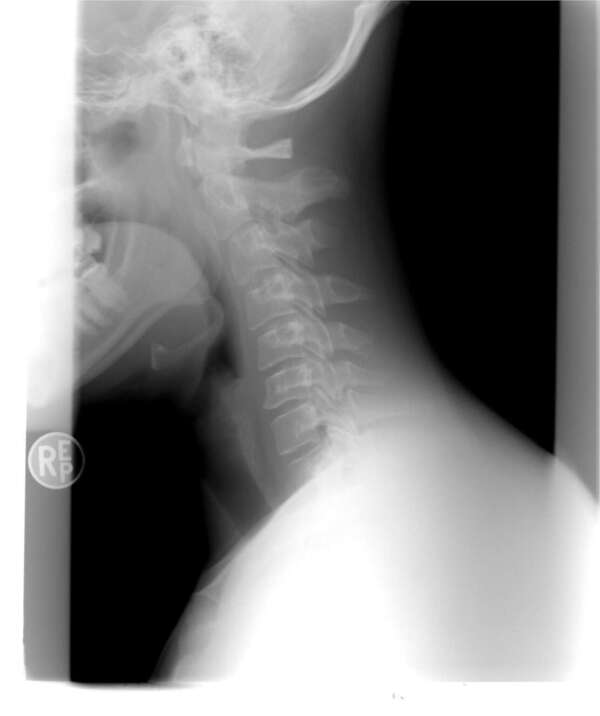

La chiropraxie est une profession de la santé. Elle se fonde sur une conception globale du fonctionnement de l’organisme et des relations existant entre la colonne vertébrale, le système nerveux et certains troubles de santé. Elle prend ainsi en compte les facultés de récupération du corps humain. Elle a pour objet la détection, la correction et la prévention des dysfonctionnements de l’appareil locomoteur et de ses conséquences, notamment au niveau de la colonne vertébrale et des membres.

Le chiropracteur pourra vous proposer une prise en charge optimale si vous lui présentez, lors du premier rendez-vous, les radios et bilans médicaux antérieurs.